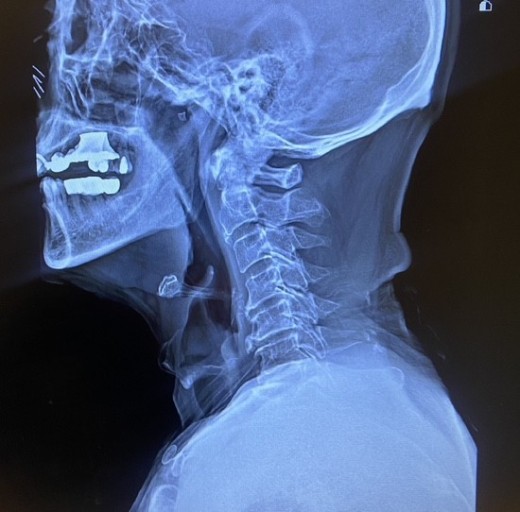

목디스크 증상 목디스크란 목 뼈 사이의 디스크가 원래의 자리에서 이탈하면서 신경을 누르거나 뼈조직이 비정상적으로 자라나 목을 지나가는 척추신경을 누르게 됨으로써 통증을 느끼는 질환입니다. 예전에는 40대 이상의 분들한테서 주로 나타나는 질환이었지만 요즘은 젊은 세대에도 흔하게 볼 수 있는 질환이 되었습니다.

외부로부터 강력한 충격은 주로 교통사고로 인해서 발생돼요. 교통사고만 나면 주로 목을 잡게 되죠? 뒤차에 받혔을 때 주로 경추에 충격을 주어 주로 경추염좌 진단을 받는데 가벼운 증상일 때 빨리 치료를 해야 되므로 입원해서 치료를 받는 게 좋다. 퇴형성으로 목 디스크 증상이 조금씩은 다 있는데 이럴 때 교통사고 나면 전문기관 가서 X-Ray 촬영하다 보면 디스크(경주 염좌) 진단을 받게 됩니다.